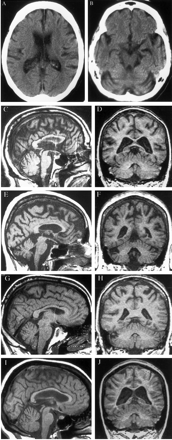

图2。t1加权磁共振成像与SCA-12选定的家庭成员。(A, B)头部CT的渊源者,一个64岁的女人(病人III-5) 60岁,4年前以前描述的神经系统检查。CT显示中度小脑和大脑皮质萎缩和侧脑室扩大真空交货。(C, D)大脑核磁共振的64岁的老人(病人III-10)拍摄的时候前面描述的神经系统检查。矢状面MRI (C)显示轻度小脑萎缩与保护脑干体积。冠状图像(D)显示中度脑皮层,皮层下白质、小脑萎缩和侧脑室扩大。基底神经节和其他皮层下灰质区域(图中未显示)并不明显萎缩。59岁的女人(E, F) MRI(病人III-8)当时她的神经系统检查揭示中度脑皮质和小脑萎缩影响小脑蚓体侧小脑半球。(G H) MRI的41岁的男人(病人IV-11)在他的神经系统检查揭示轻中度小脑和大脑皮质萎缩。40岁的女人(I, J) MRI(病人IV-12)时,她的神经系统检查。矢状图像(I)显示轻度小脑萎缩但正常脑干体积。冠状核磁共振(J)揭示了大脑皮层和皮层下萎缩与侧脑室扩大真空交货。

渊源者的脑CT和MRI 4影响家庭成员(见图2)轻中度萎缩的大脑皮层和相对保护脑干和小脑皮层下灰质区域。